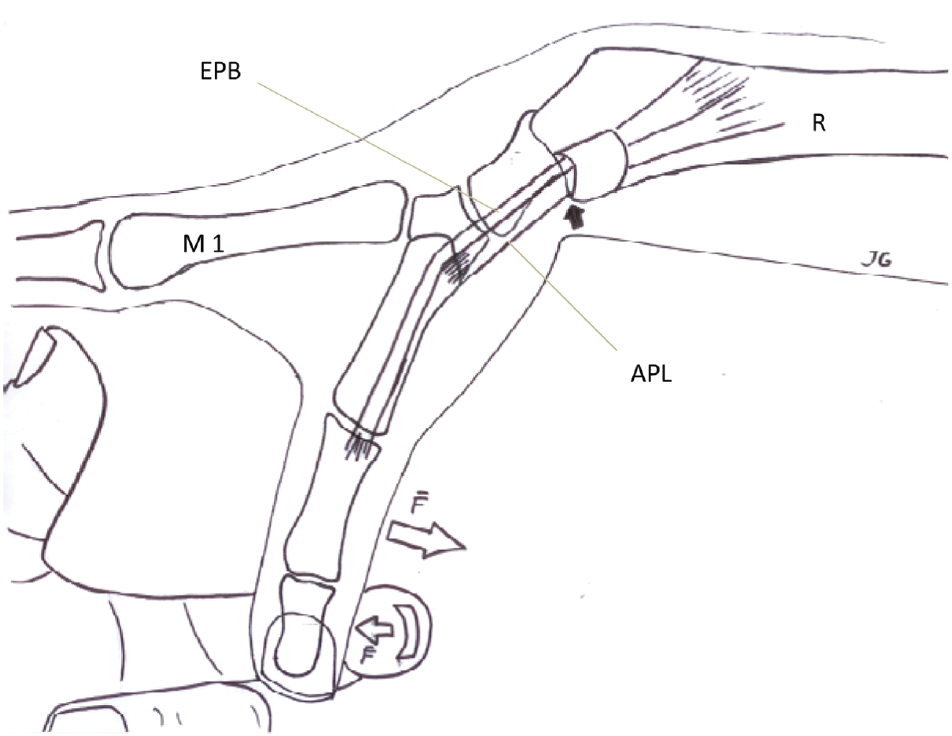

标题:了解 De Quervain 的病理学:特殊测试的综合探索

了解 De Quervain 的病理学:对特殊测试的全面探索作者:Miranda Materi De Quervain 的和特殊测试 De Quervain 腱鞘炎是一种以...

手部治疗文章评论:径向协同测试,有助于诊断奎文氏腱鞘炎

Chihua, L.、Langford, PN、Sullivan, GE、Langford, MA、Hogan, CJ 和 Ruland, RT (2021) 径向协同测试:辅助诊断 de Quervain 腱鞘炎。 ...

更好的 De Quervain 腱鞘炎测试

JF Goubau、L. Goubau、A. Van Tongel、P. Van Hoonacker、D. Kerckhove、B. Berghs (2013)。手腕过度屈曲和拇指外展(什么)测试:...